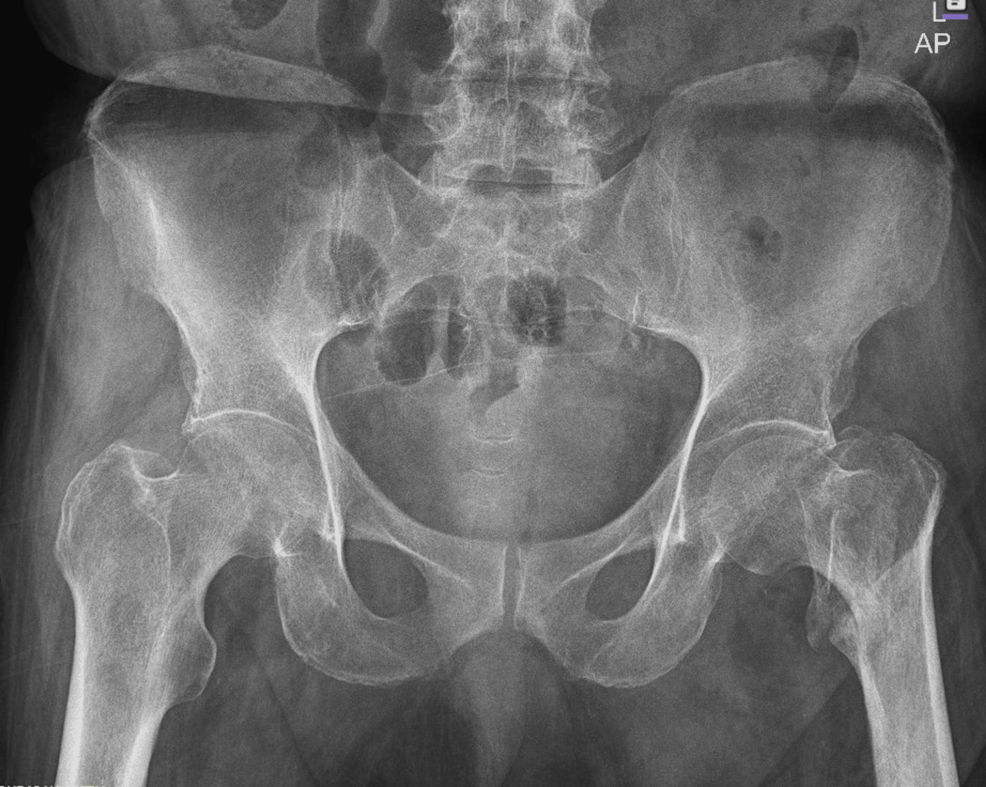

An 80-year-old male presented to the Emergency Department following a fall resulting in a closed left femoral neck fracture. He was scheduled for closed reduction and internal fixation with a trochanteric femoral nail advanced (TFNA) as confirmed by X-ray pelvis showing a “mildly displaced intertrochanteric fracture of left femur” (Figure 1). His medical history included coronary artery disease with prior coronary stenting (echocardiography revealed preserved systolic function (ejection fraction 55-60%), Grade I diastolic dysfunction, and no valvular lesions, regional wall motion abnormalities, or pulmonary hypertension, indicating low perioperative risk for anesthesia), poorly controlled hypertension, end-stage renal disease requiring twice-weekly hemodialysis, and well-controlled type 2 diabetes mellitus. Additional conditions included benign prostatic hyperplasia, bilateral renal cortical cysts, and cystitis. His medications comprised bisoprolol, aspirin, enoxaparin (substituted for clopidogrel preoperatively), insulin, ezetimibe, and topical beta-sitosterol, with no reported drug allergies.

Preoperative evaluation classified the patient as American Society of Anesthesiologists (ASA) physical status 3, reflecting severe systemic disease. The Revised Cardiac Risk Index (RCRI) score indicated Class III, with a major adverse cardiac event risk exceeding 10.1% [4]. Electrocardiography showed sinus rhythm with right bundle branch block (Figure 2), while chest radiography was unremarkable. Airway assessment revealed a Mallampati Class II score, full cervical mobility, and removable partial dentures. Laboratory findings (Table 1) included elevated serum creatinine (4.98 mg/dL), mild hyperkalemia (5.7 mmol/L), mild anemia (hemoglobin of 11.6 g/dL), and a normal international normalized ratio (INR: 1.00). Imaging confirmed the femoral neck fracture, with ultrasonography noting renal cysts (Figure 3) and prostatic enlargement (Figure 4). An echocardiogram was normal (Figure 5). Cardiology consultation advised continuing bisoprolol, resuming aspirin postoperatively, and bridging anticoagulation with enoxaparin, discontinued 24 hours preoperatively. Recent hemodialysis stabilized electrolytes, optimizing the patient for surgery.